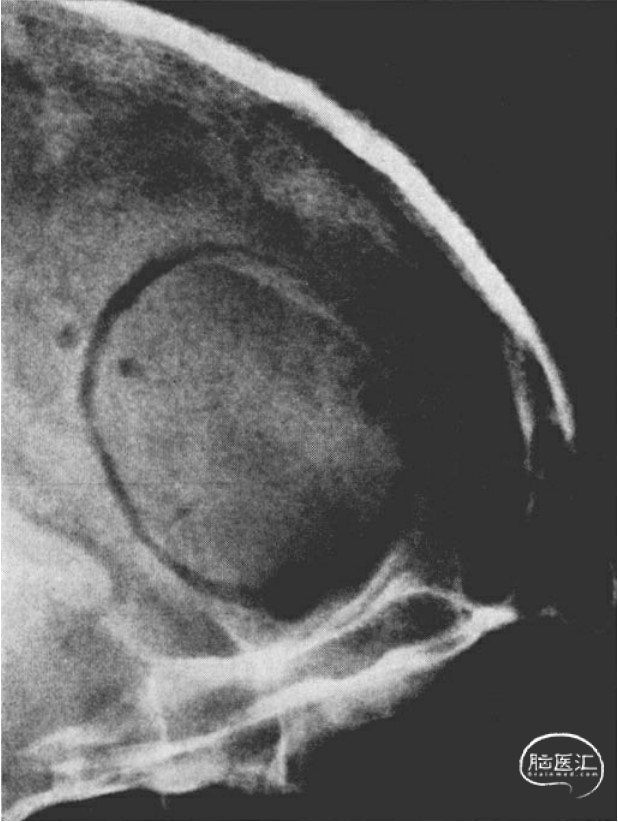

颅底的颅内视图,显示患者头部转动的角度,以允许手术显微镜垂直接近。

颅底相应的X射线照片,以说明平行于眶侧壁的视神经的角度。